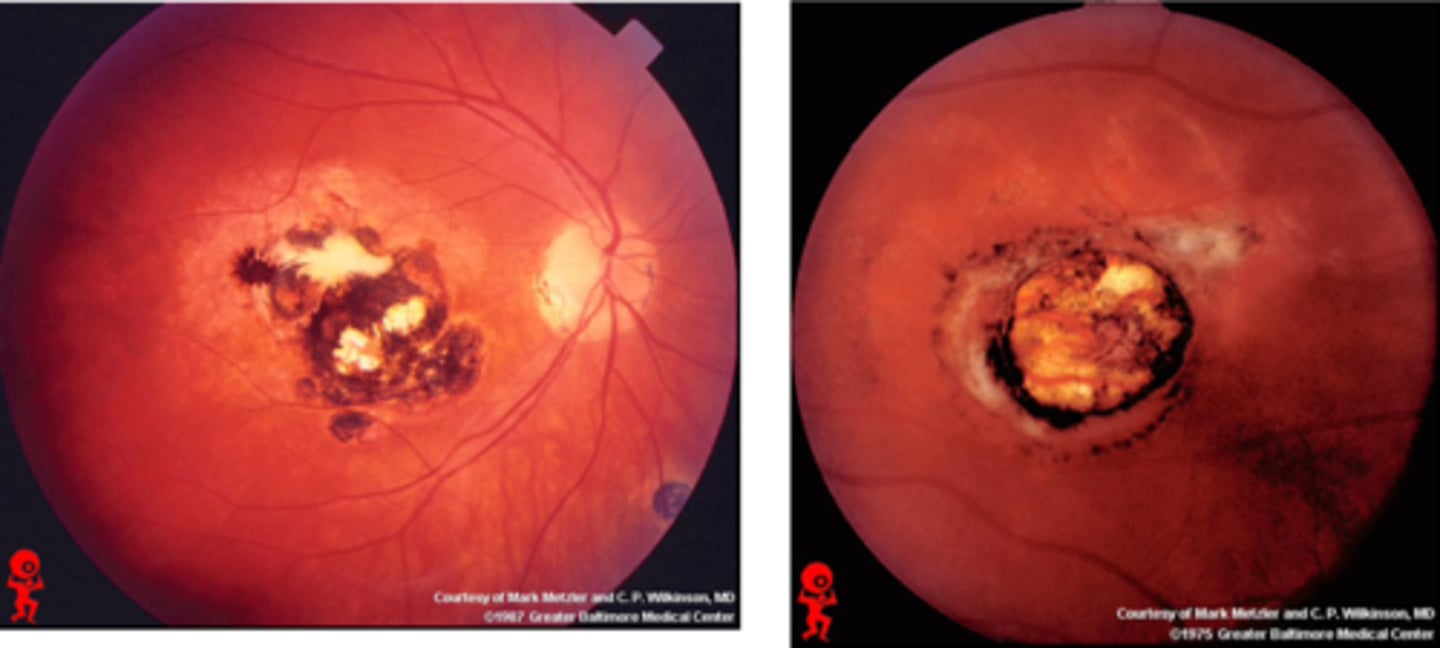

What findings of toxoplasmosis are seen here?

latent scars